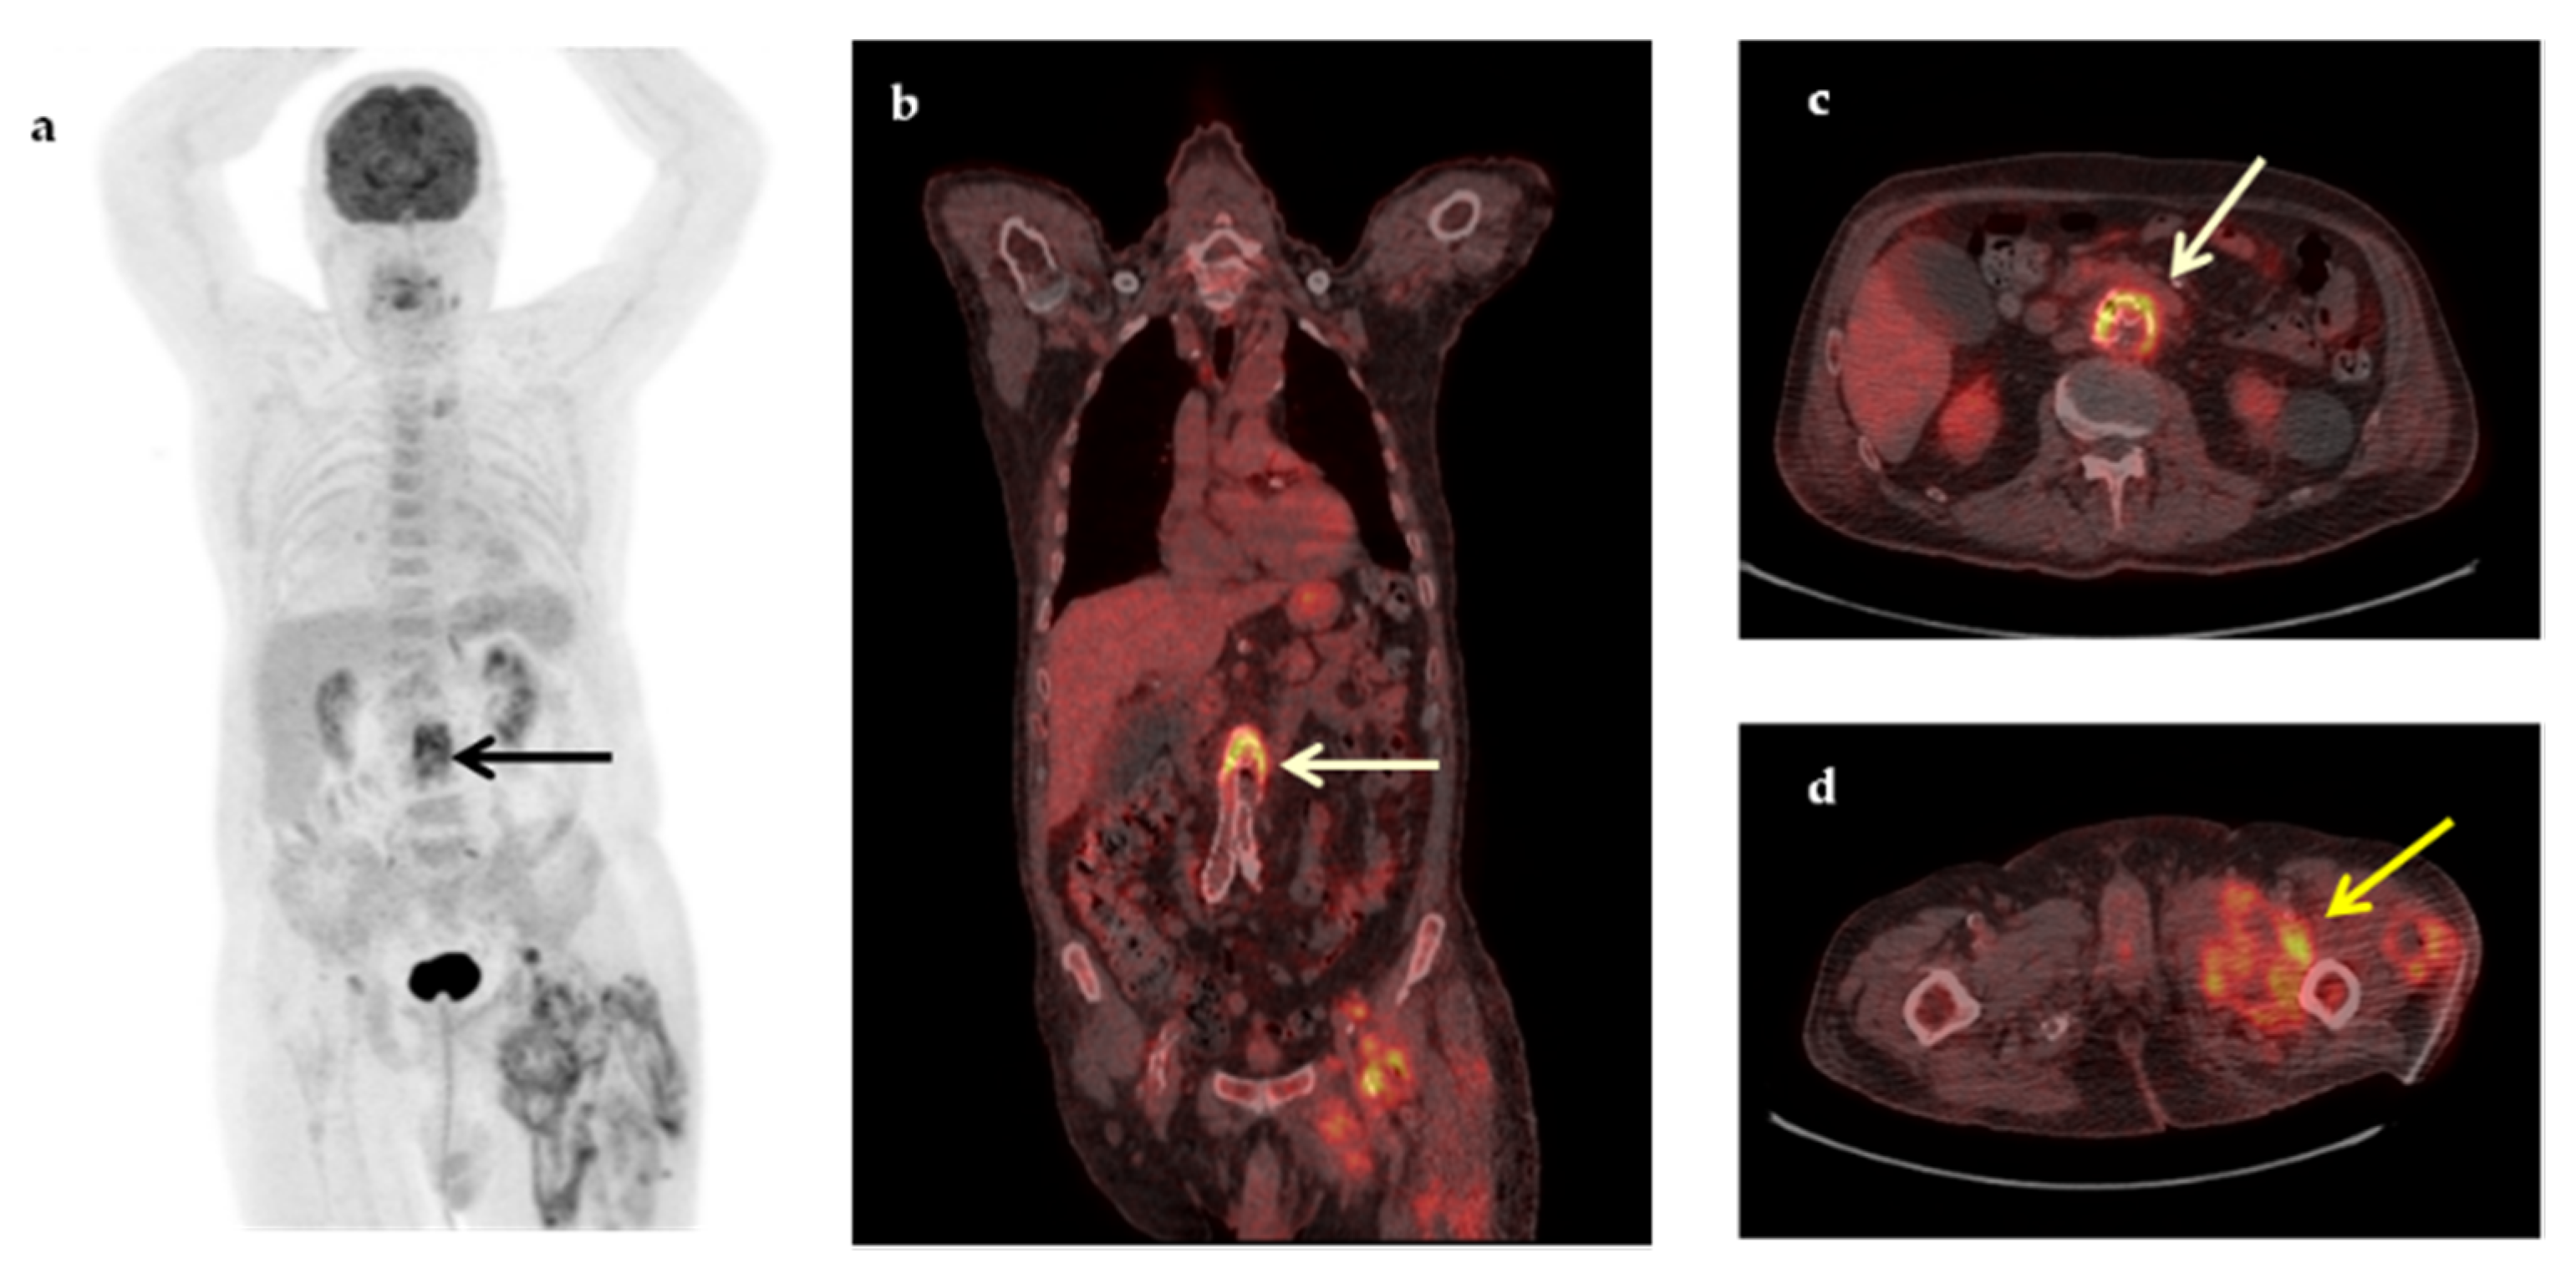

| Infections | 20 (40%) |

| Abdominal abscesses | 4 |

| Infectious cyst in polycystic renal disease | 3 |

| Pneumonia/inflammation of bronchiectasis cysts | 3 |

| Vascular graft infection | 3 |

| Tuberculous spondylitis | 1 |

| Bacterial spondylodiscitis | 1 |

| Pulmonary tuberculosis | 1 |

| CIED-associated infection | 1 |

| Infectious lymphadenopathy | 1 |

| Cryptococcosis | 1 |

| Leishmaniasis | 1 |

| Malignancy | 8 (16%) |

| Non-Hodgkin’s lymphoma | 5 |

| Hodgkin’s disease | 1 |

| Lung cancer | 1 |

| Relapse of urinary tract carcinoma | 1 |

| Non-infectious Inflammatory diseases (NIID) | 11 (22%) |

| Large vessel vasculitis/Takayasu’s arteritis | 3 |

| Adult-onset Still’s disease | 2 |

| Sarcoidosis | 1 |

| Polymyalgia rheumatica | 1 |

| Inflammatory bowel disease | 1 |

| Familial Mediterranean fever | 1 |

| Neo-esophagus inflammation from gastroesophageal reflux | 1 |

| Subacute thyroiditis | 1 |